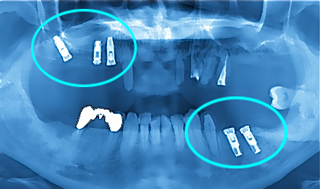

【術前のレントゲン】

最小限の放射線量で鮮明な画像をひきだす「デジタルレントゲン機」を用いて、インプラントの植込み位置と深さをシュミレーション化。

【術後のレントゲン】

上顎に3本、下顎に2本のインプラント体が、予定の位置、長さに上手く入りました。本日はドキドキ緊張の中、お疲れ様でした。